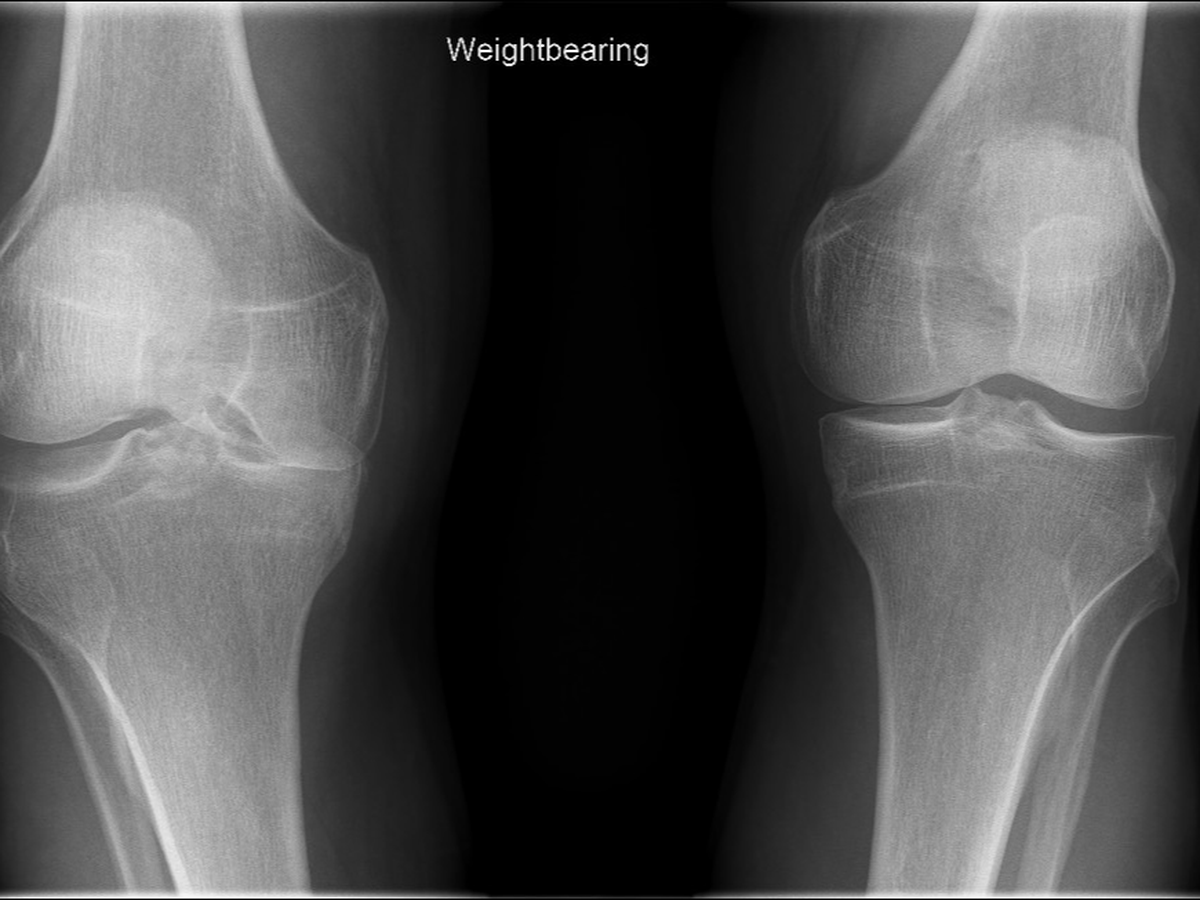

Since 2019, I have had issues with my right knee. Upon initial x-rays, it showed that it was mild osteoarthritis and a small bone chip floating in my knee. At the time, doctors advised me that it was nothing to worry about, take an Advil and carry on.

Since then it has progressed to severe degradation of my knee (bone on bone) and up until most recently I was repeatedly told to just take some painkillers. The 24/7 pain and the inability to do things that I normally would do (work/bicycling/hiking) is emotionally and physically draining.